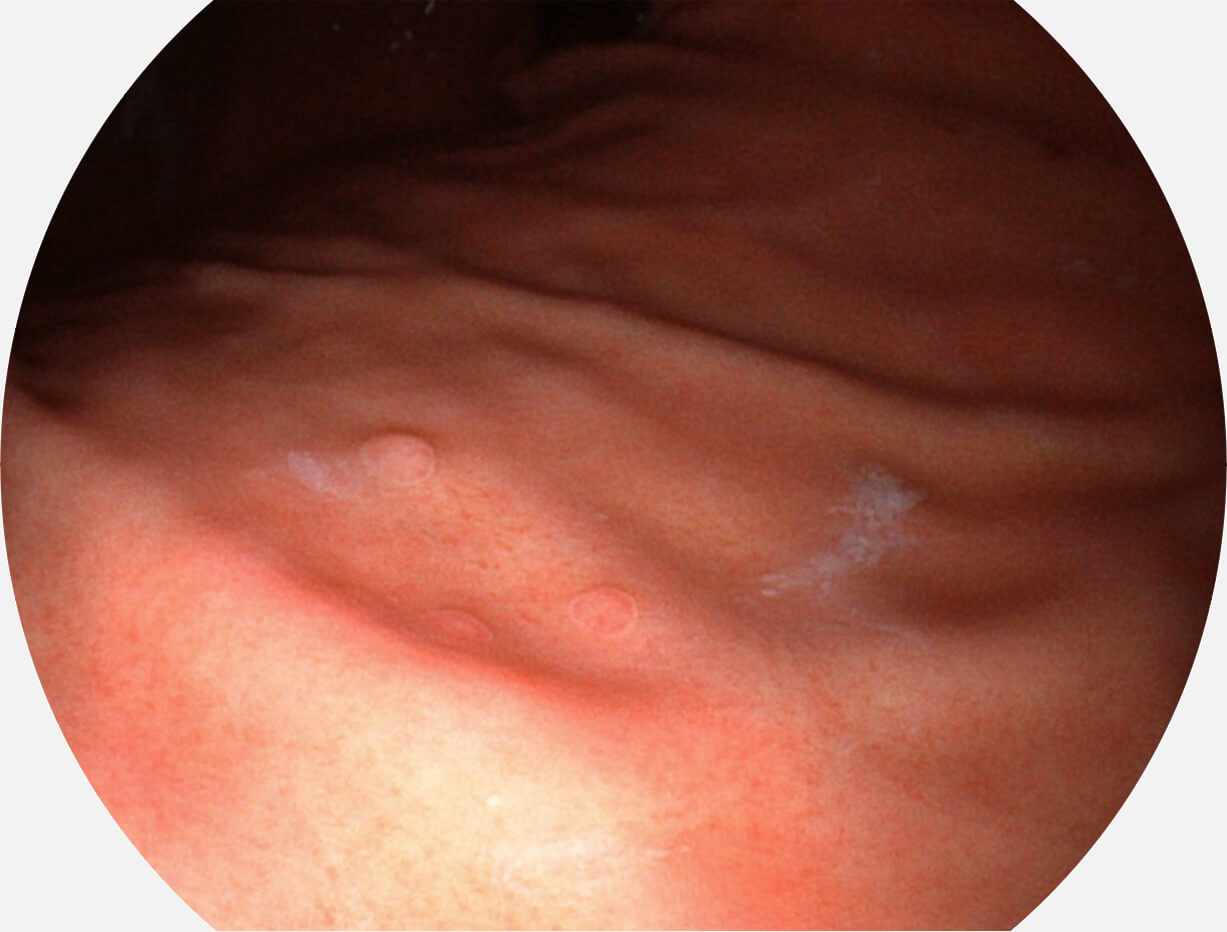

图像具有高亮度、高黏膜血管颜色对比度的特点,且不改变粘液、食物残渣、粪便的基本颜色,可在中远景下进行观察,助力消化道早期疾病的诊断。

• 白光图像 SFI图像